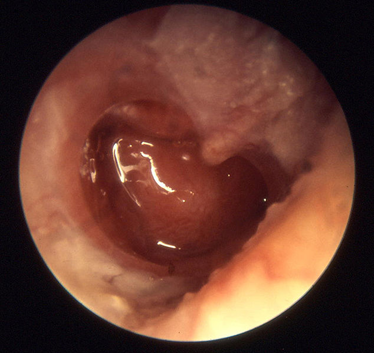

Imagen capturada por la autora, con dispositivo Samsung, durante una evaluación del oído con un otoscopio

La membrana timpánica tiene una coloración rosado pálida; en el caso de una OME, esta puede lucir con pérdida de su luminosidad, con líquido amarillento, anaranjado o blanquecino en la caja timpánica, presencia de burbujas, o incluso estar retraída, tratándose entonces de una atelectasia.

Observen la diferencia en la apariencia de estas membranas timpánicas; la primera nos muestra un oído normal y la segunda una OME. Ambas imágenes fueron capturadas con endoscopio rígido marca Olympus de la autura y editadas con el programa Microsoft Power Point.